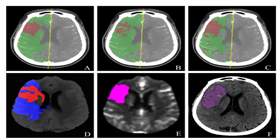

已应用于西医医疗设备医疗诊断和中医诊断,,,,为诊疗提供辅助决策支持。。。。